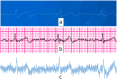

The use of technology in healthcare is one of the most critical application areas today. With the development of medical applications, people's quality of life has improved. However, it is impractical and unnecessary for medium-risk people to receive specialized daily hospital monitoring. Due to their health status, they will be exposed to a high risk of severe health damage or even life-threatening conditions without monitoring. Therefore, remote, real-time, low-cost, wearable, and effective monitoring is ideal for this problem. Many researchers mentioned that their studies could use electrocardiogram (ECG) detection to discover emergencies. However, how to respond to discovered emergencies in household life is still a research gap in this field.•This paper proposes a real-time monitoring of ECG signals and sending them to the cloud for Sudden Cardiac Death (SCD) prediction.•Unlike previous studies, the proposed system has an additional emergency response mechanism to alert nearby community healthcare workers when SCD is predicted to occur.